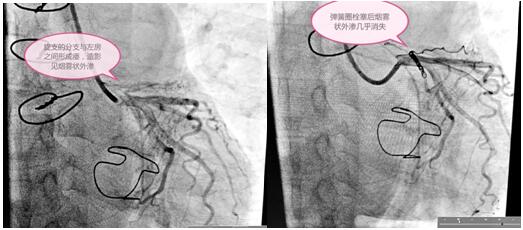

定于3月3日進行冠狀動脈瘺彈簧圈栓塞手術,術前手術團隊為患者細心指導,消除患者緊張情緒,穿著手術衣,帶著一次性手術帽和普通外科口罩,做好防護。吳棟梁院長和高勝利主任手術團隊為患者精心進行了手術,要將大小合適的彈簧圈放在血管遠端狹窄處封住瘺口,患者冠脈及分支血管比較迂曲,會導致手術過程比較復雜,耗時長,這些在手術方案里均考慮到。初始常規使用的導絲通過困難,后來根據患者血管走形我們又選擇了微導管和特殊的導絲,導管室很安靜,能聽到的只有時鐘的滴答聲和我的心跳聲,調整了手術器械后彈簧圈很快送到位并釋放,手術終于圓滿結束,比我們預計的手術時間提前了半小時。

術前與術后